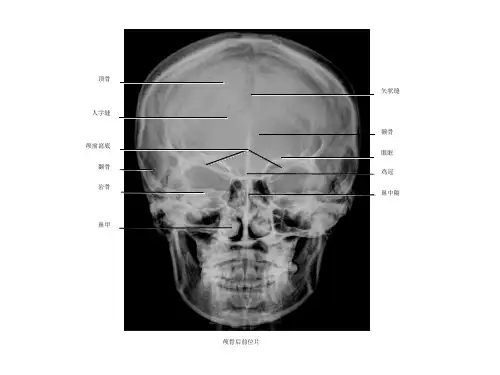

颅底解剖结构

颅底CT影像